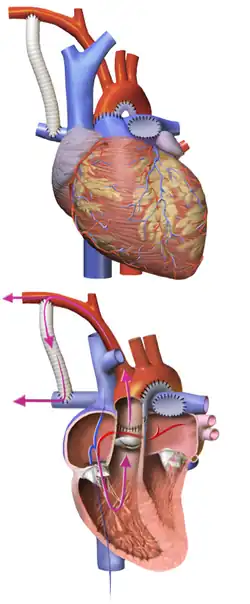

Providing systemic circulation

The main pulmonary artery is separated from the left and right portions of the pulmonary artery and joined with the upper portion of the aorta. Widening of the pulmonary artery is often necessary, and may be accomplished by using the patient's existing biological tissue, or appropriate animal tissue. This allows the blood, a mixture of oxygenated and deoxygenated, to be pumped to the body via the morphologic right ventricle, through the pulmonary valve. At this point in the surgery, the right ventricle is directly connected to systemic circulation through the Neoaorta or the reconstructed aortic outflow track. Second step of the procedure establishes blood flow to the lungs.[20]

Providing pulmonary circulation

Variations to this step have been proposed over the years, however only two have been adapted in general practice over the last 20 years. In both cases a conduit is used to direct blood flow into the lungs, however anatomic anchoring varies. There are two different types of shunts used during the procedure: Modified Blalock Taussig or (MBTS) and right ventricle- to pulmonary artery shunt (RVPA or Sano shunt). MBTS shunt provides connection from the pulmonary artery to brachiocephalic artery or subclavian artery, while the RVPA conduit provides connection from right ventricle to pulmonary artery.[21][5]

- Blalock-Taussig Shunt, a Gore-Tex conduit (a kind of plastic tubing) is used to connect the subclavian artery to the pulmonary artery. In this case blood comes from the single ventricle, through the pulmonary valve, the reconstructed aorta, the subclavian artery, and the conduit, to the lungs. There are variations on this procedure where the origin of the shunt is elsewhere in the systemic circulation (e.g. from the aorta itself) rather than the subclavian artery.

- With a Sano shunt, an incision is made in the wall of the single ventricle, and a Gore-Tex conduit is used to connect the ventricle to the pulmonary artery. Direct canalization to the right ventricle provides pulsatile blood flow compared to the Blalock-Taussig conduit.